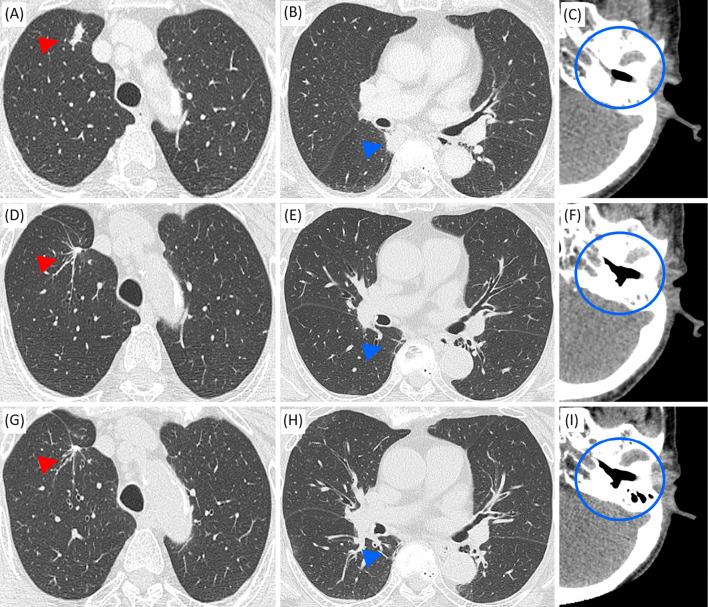

Granulomatosis with polyangiitis (GPA) is characterized by necrotizing granulomatous lesions and is classified as ANCA-associated vasculitis (AAV). We herein report a case of GPA that was remitted by resection of a pulmonary lesion without immunosuppressive therapy. We detected activated neutrophils and neutrophil extracellular traps (NET) formation in resected lung tissue by immunofluorescence. Activated neutrophils and NETs might be involved in the pathophysiology of AAV and induce the vicious cycle of ANCAs and NETs. In cases of GPA with no other severe lesions, the reevaluation of the disease activity after diagnostic resection is crucial for considering the need for immunosuppressive therapy.

肉芽肿性多血管炎(GPA)的特征为坏死性肉芽肿性病变,属于抗中性粒细胞胞质抗体相关性血管炎(AAV)。本文报告了一例 GPA 患者,其肺部病变通过手术切除后无需免疫抑制治疗即可缓解。我们通过免疫荧光检测到切除的肺组织中存在活化的中性粒细胞和中性粒细胞胞外诱捕网(NET)的形成。活化的中性粒细胞和 NET 可能参与 AAV 的病理生理学,并诱导 ANCAs 和 NETs 的恶性循环。对于无其他严重病变的 GPA 病例,在诊断性切除后重新评估疾病活动度对于考虑是否需要免疫抑制治疗至关重要。